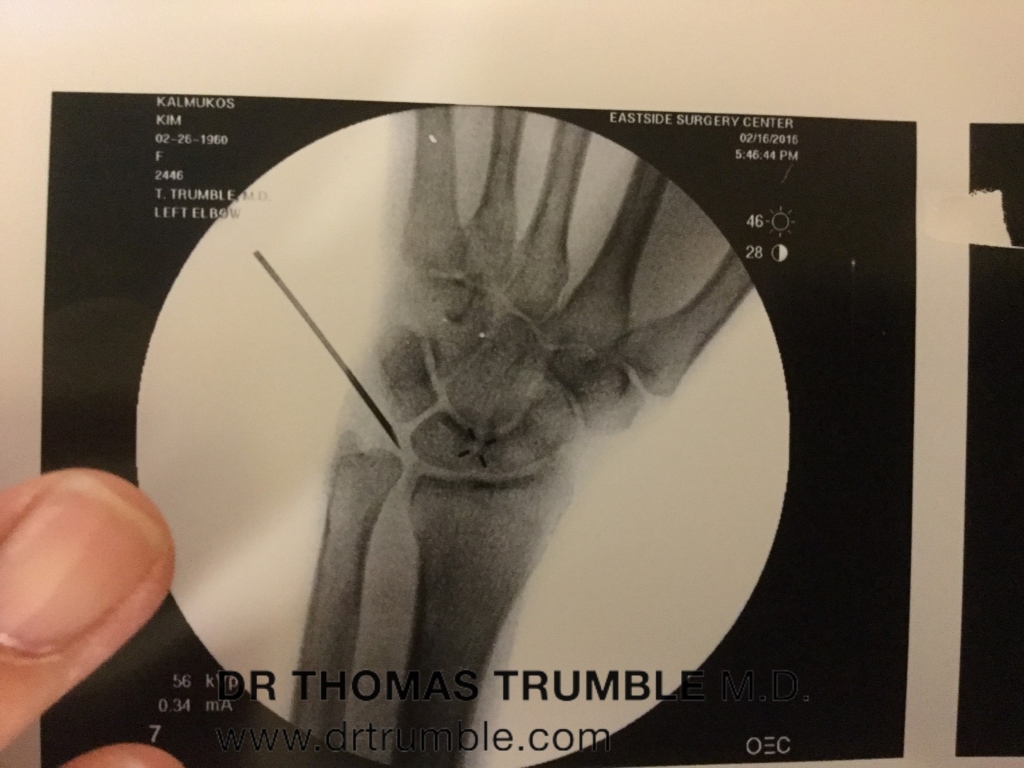

Here are his surgical photos: (click on images to enlarge) Photos in order left to right from incision to finishing up with PRP(Platelet Rich Plasma) Injections and Fluoroscopic Images.

Dr. Trumble told my lady friend after surgery, there was a good size scar tissue that had to be removed besides anchoring the torn LCL ligament and ECRB(Extensor Carpi Radialis Brevis) tendon on the lateral epicondyle. None of this was seen on 2 previous MRI’s. Dr. Trumble had relied upon my detailed subjective history along with his objective tests using ultrasound and stress fluoroscopy for proof of my instability of my elbow.